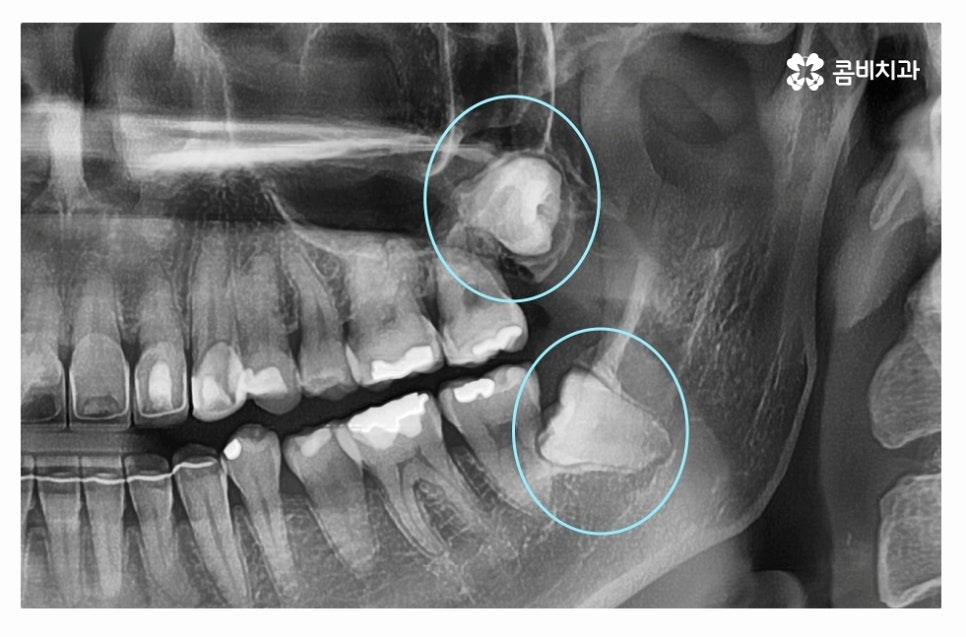

다음 사례를 살펴보면 위 사례와 마찬가지로 사랑니가 정상적으로

맹출 되어 있지 않고 어금니 뿌리 쪽으로 자라고 있는데요

위 환자분의 경우 사랑니와 어금니 사이에 충치가 발생하여

어금니 손상까지 (엑스레이상 좌측 위 사랑니) 유발된 사례라고 할 수 있어요.

사랑니의 경우 발치를 하면 되지만 어금니는 평생 지켜야 한다는 점에서

치아 수명이 줄어들게 되니 안타까운 상황이라고 할 수 있는데요.

사랑니로 인해 충치가 발생한 좌측 위 사랑니도 발치를 진행했지만

우측 사랑니도 위치가 좋지 않아서 누운사랑니발치 진행하였고

사랑니로 인해 충치가 발생된 어금니의 경우 크라운 치료를

해야 했던 만큼 사랑니는 주기적으로 검진이 필수라고 할 수 있어요.